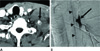

Fig. 4

A 74-year-old man with car accident injury.

A. Contrast-enhanced CT scan shows contrast extravasation (arrow) with large amount of surrounding hematoma formation in left lower neck and supraclavicular area.

B. Selective angiography shows contrast extravasation (arrow) from small branch of left thyrocervical trunk supplying anterior spinal artery (arrowheads). We could not do embolization because of the risk of spinal cord infarction.